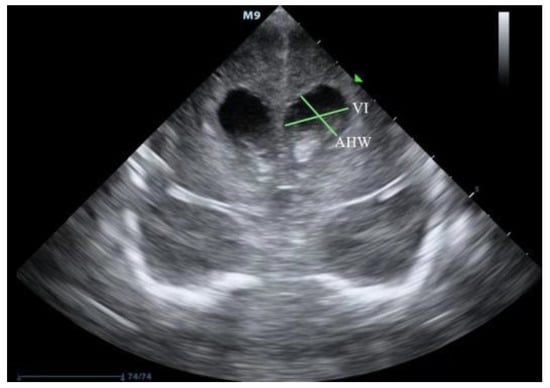

2. Ultrasound Diagnosis of PHVD